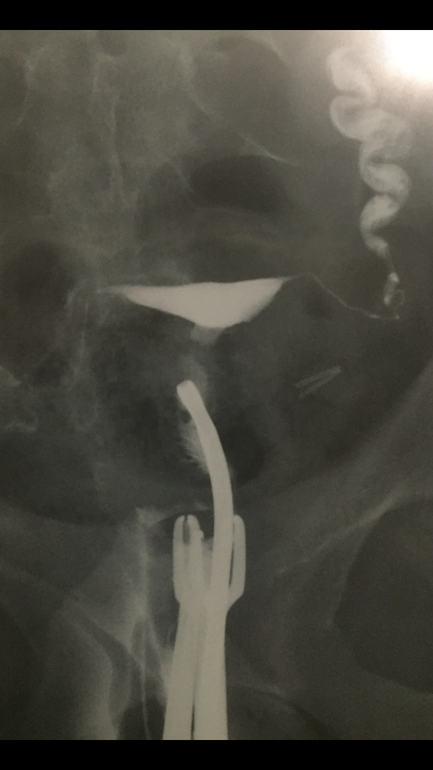

Результат ГСГ!!!

Спасибо большое))) а самое интересное, что когда первая доза контраста была врач сказа одна труба не прошла и после ГСГ уже настоятельно рекомендовала операцию, но на первом снимке она тоже прошла!!! Сейчас добавлю фото

Справа в этих "клубах дыма" видно лицо ребенка,приглядитесь))) это точно знак!)))